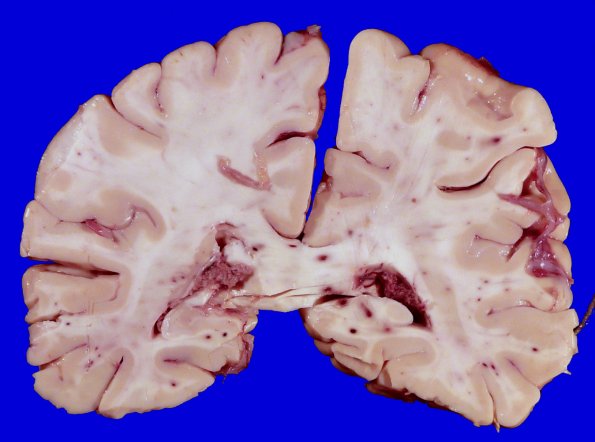

12A1-3 Several coronal sections were remarkable for numerous petechial hemorrhages mostly confined to the white matter suspicious for fat emboli.